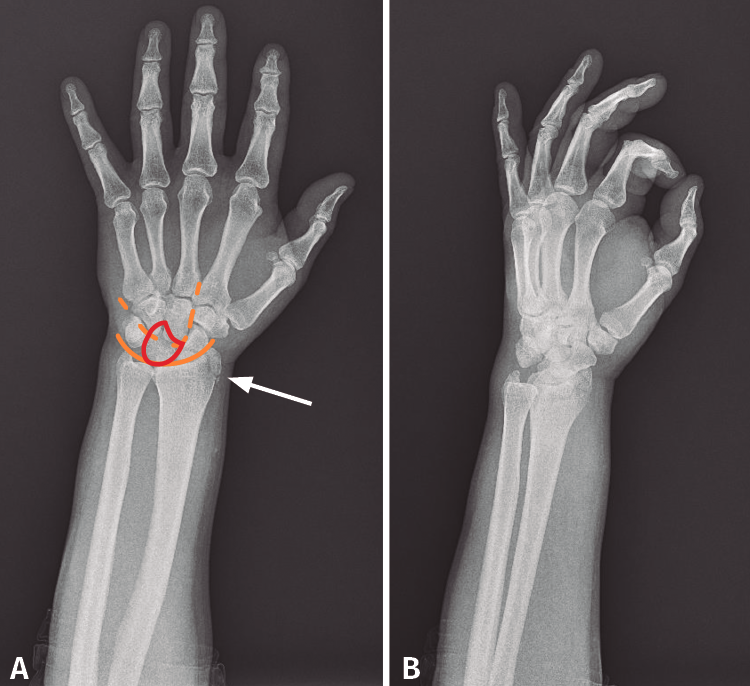

Desde el Servicio de Urgencias se solicita un radiografía anteroposterior y oblicua de mano, muñeca y tercio distal del antebrazo izquierdo. Si observamos detenidamente la radiografía anteroposterior, se observa una alteración en los arcos de Gilula y una posición alterada del semilunar (flexión palmar). Debido a que estas radiografías no son las más adecuadas para el estudio de la muñeca, podría pasar desapercibida la lesión (Figura 1).

Figura 1. Radiografía (A) anteroposterior y (B) radiografía oblicua de mano, muñeca y tercio distal del antebrazo realizadas durante la atención en urgencias inicial. Se observa la fractura de la estiloides radial (flecha). Alteración en los arcos de Gilula (línea). Alteración en la forma del semilunar, en flexión volar (rojo).